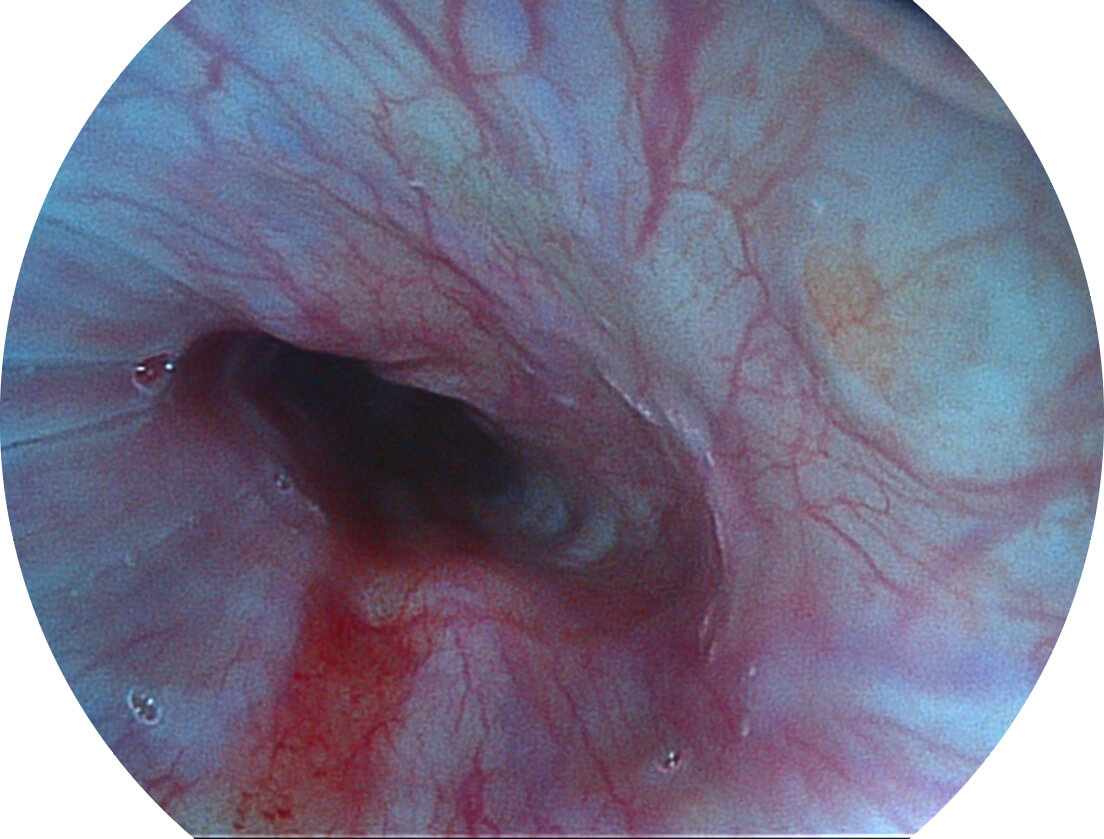

VIST图像